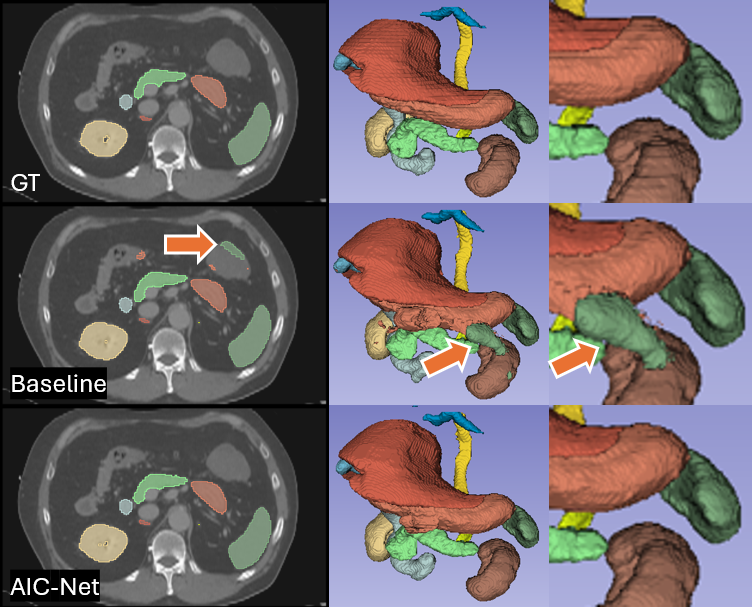

Figure 7: Qualitative comparisons on organ segmentation. The baseline method is suboptimal, resulting in the segmentation of additional spleen tissue, as indicated by the orange arrows.

Figure 8: Qualitative comparisons on organ segmentation. The baseline method (actually all baseline backbones) incorrectly segments the adrenal gland, as shown by the blue arrows.

Qualitative Comparison

The learned common prior, as well as accurate deformation, in our AIC-Net can promote anatomically accurate segmentation. This is supported by results in Figures 6, 7 and 8. In Figure 6, despite being over-smoothed, the deformed prior at the global level still provides accurate guidance for identifying vertebra indices, which in turn supports precise segmentation at the local level. In contrast, the baseline method appears to struggle with correctly identifying vertebra indices, leading to inconsistent predictions. We also observe that this mixing effect is a common issue in bone segmentation tasks (Wasserthal et al. 2023). In Figures 7 and 8, baseline methods give incorrect segmentation that result in separated spleen and left adrenal gland, which clearly violate human anatomy. For both cases, AIC-Net gives correct predictions.